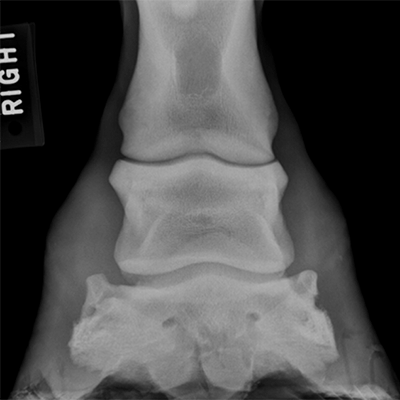

Her: His side bones in both feet are wild

Sidebones are the ossification of collateral cartilage in hoof. It is extremely common – some estimates suggest 80% of all horses have it. 95% of the time, it causes no issues and is not a contributing factor to lameness.

“However, fracture of these cartilages or damage to nearby ligaments may be an issue when lameness is localized to the foot.”

“There are reports of sidebone associated with changes to ligaments elsewhere on the limb, suggesting that sidebone may cause abnormal stress during movement.”

“If the condition is extensive enough, you should carefully consider this horse’s future and be aware that he is at-risk for collateral ligament, distal interphalangeal (coffin) joint, and distal phalanx (pedal bone) injury,”

I looked up an image of a normal hoof x-ray:

Now here is Griffy’s – see if you can spot the difference, it’s subtle: